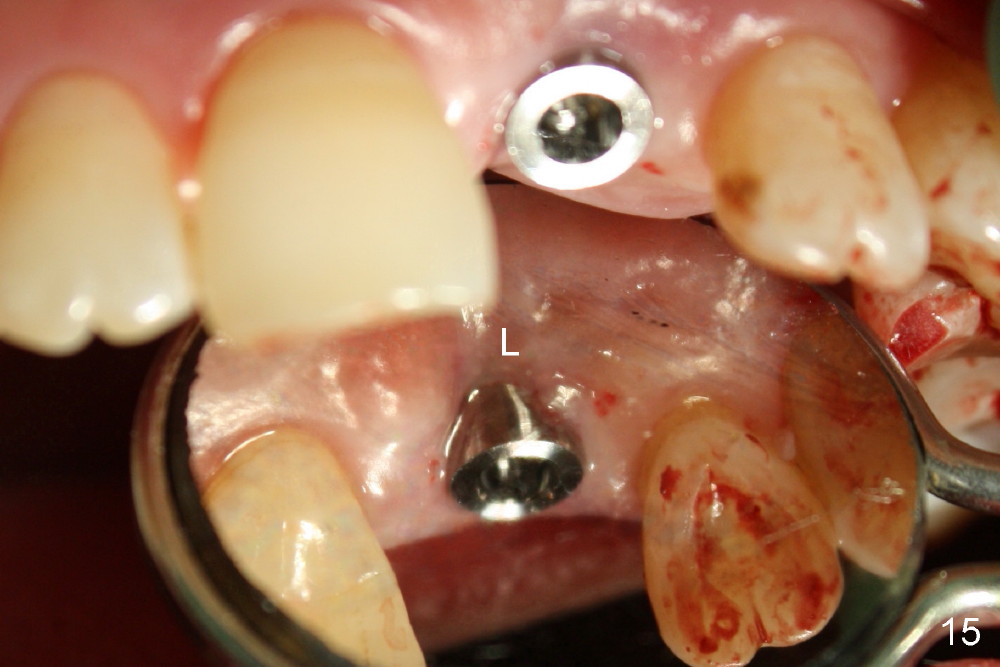

A 60-year-old lady had an abscess mesial to #9 six years ago (Fig.1,2 <), treated as a perio lesion by laser (Fig.3) and osseous surgery without bone graft (Fig.6, followed by CT exam revealing semi-circumferential bone loss (Fig.4,5). When the perio treatment failed, attention was paid to endo aspect (Fig.7-9). In fact the pulp was found to be vital when access to root canal therapy was made. As expected, the treatment failed again. The palatal fistula persisted. The infection was suspected to be a source of remote immediate implant site (#30). The tooth #9 was extracted. It appears that there is a semilunar crack line in the linguomesial root (Fig.12). When the socket healed 2 weeks post extraction (Fig.10), the #30 buccal defect was debrided with bone graft. There was no bone resorption 4 weeks post extraction (Fig.11); a 4.5x17 mm implant was placed (Fig.13-15). An immediate provisional was fabricated (Fig.16-18). Fig.19,20 were taken 3 months post implantation and 7 months post cementation, respectively. Dense bone forms around the implant coronally 4 years 5 months post cementation (Fig.21), while the gingiva is healthy palatally (Fig.22) and buccally (Fig.23).